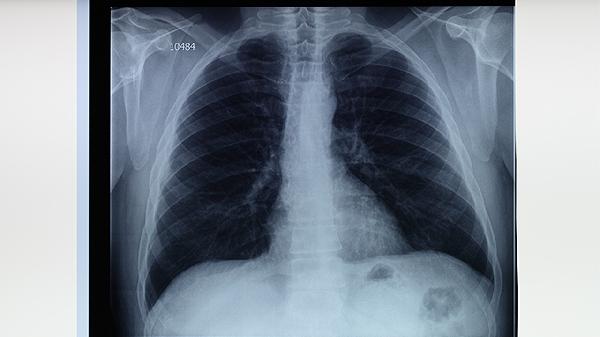

肺結(jié)核是如何傳染的呢

肺結(jié)核主要通過呼吸道飛沫傳播,當患者咳嗽、打噴嚏或說話時,含有結(jié)核分枝桿菌的飛沫被健康人吸入后可能導致感染。肺結(jié)核的傳播途徑主要有與患者密切接觸、處于通風不良環(huán)境、免疫力低下等。

肺結(jié)核患者在咳嗽、打噴嚏或大聲說話時,會釋放含有結(jié)核分枝桿菌的微小飛沫。這些飛沫可在空氣中懸浮數(shù)小時,被周圍人群吸入后,細菌可能定植于肺部。飛沫傳播是肺結(jié)核最主要的傳染方式,尤其在密閉、擁擠且通風差的環(huán)境中傳播風險顯著增加。